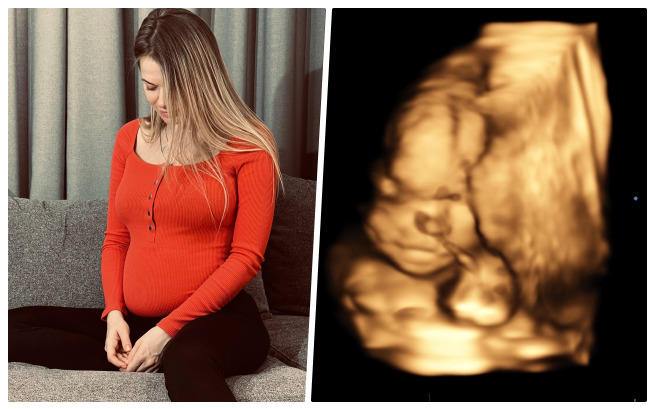

Euforia, że już niedługo wezmę na ręce swoje maleństwo, zawróciła mi w głowie. Dbałam o siebie ze wszystkich sił... Regularnie robiłam wszystkie potrzebne badania, odwiedzałam lekarzy, dużo spacerowałam i wyobrażałam sobie moment, w którym pierwszy raz przytulę moją kruszynkę. Nie potrafię opisać, co czułam, gdy po raz pierwszy w życiu usłyszałam na USG serce dziecka... Gdy usłyszałam „Gratuluję, będziesz mieć zdrową dziewczynkę ”. Codziennie rozmawiałam z moją córeczką... Mówiłam jej, jaki kolor będzie mieć jej pokój, jak będziemy spędzać wakacje u babci, że będziemy mieć psa...

Szłam na kolejne badanie USG... Pamiętam, że mój mąż ubierał choinkę, że czekały pod nią nowe zabawki, które kupiliśmy maleństwu... Wychodziłam z uśmiechem na ustach, wyobrażając sobie, że kolejne Święta spędzimy już we trójkę. Wracałam zrozpaczona, ze złamanym sercem... USG. Gabinet. Długa cisza... A potem słowa lekarza. Powiedział, że nie może zrozumieć, dlaczego nie widzi prawej strony przepony i że widzi jakiś dziwny cień w miejscu prawego płuca... Dostałam skierowanie na szczegółowe badania. Mąż towarzyszył mi tym razem, podczas badania USG oboje płakaliśmy i nie mogliśmy przestać...

Nasza córeczka ma jedną z najcięższych wad, rozpoznawanych w ciąży - prawostronną przepuklinę przeponową... To bardzo rzadka wada, która powoduje, że narządy znajdujące się w jamie brzusznej przesuwają się do klatki piersiowej, powodując zakłócenia w pracy płuc i serca... Wasilisę uratuje tylko operacja. Jeśli nie pomożemy jej teraz, po narodzinach czeka ją śmierć!

Dostałam skierowanie na sztuczne przerwanie ciąży. Jak jednak mogę to zrobić? Moja córeczka rośnie pod moim sercem, czuję jej ruchy - lubi, gdy jem coś słodkiego, gdy gram na pianinie, gdy śpiewam... Każdy ruch uświadamia mi, że ona żyje! Jej życie można uratować, ale poza granicami naszego kraju... Skontaktowaliśmy się ze szpitalem Sant João de Déu w Barcelonie, z doktorem Eduardem Gratakosem, który jest czołowym specjalistą chirurgii płodowej. Był jednym z pierwszych, którzy wykonali takie operacje na świecie... Powiedział, że może i wie, jak nam pomóc, że już przeprowadzał takie operacje i dzieci przeżyły, że postara się zrobić wszystko, co w jego mocy, aby uratować naszą córeczkę. Koszt operacji to jednak 171 tysięcy euro!

Na początku lutego muszę znaleźć się w szpitalu. Najpóźniej pod koniec miesiąca, kiedy będę w 28. tygodniu ciąży, lekarze muszą przeprowadzić operację... Wprowadzą specjalny balon, dzięki któremu płuca rosną i wypychają z klatki piersiowej nadmiar narządów, co po urodzeniu pozwoli na pracę płuc dziecka. Nasza córeczka może żyć!